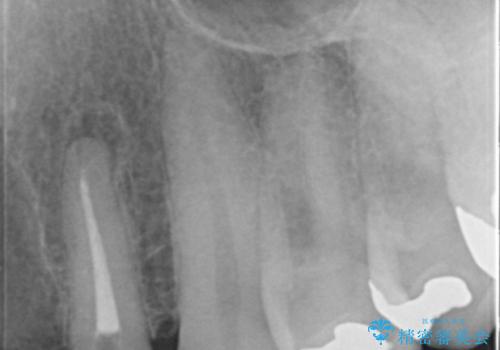

- お風呂場で転んで上の前歯が2本抜けてしまったことを主訴に来院された患者様です。

精査したところ、左上の側切歯(左上2)も破折しており保存不可能な状態でした。

左上の側切歯(左上2)を抜去し、右上の側切歯(右上2)の再根管治療後、セラミックのブリッジによる補綴を行いました。